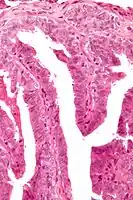

Microscopic histopathological analyses of papillary hidradenoma tumors typically reveal a nodule in the dermis, i.e. layer of skin between the epidermis and subcutaneous tissue. The tumor consists of complex patterns of interconnecting tubular and papillary (i.e. thin finger-like or frond-like) structures.[20] These structures are lined with glandular epithelial and myoepithelial cells. The glandular epithelial cells appear to be excessively proliferating in the ducts leading to the epidermis and show oxyphilic changes, (i.e. cytoplasm filled with large mitochondria, glycogen, and ribosomes) while the myoepithelial cells often appear clear cell-like, i.e. have uncolored cytoplasm when stained with hematoxylin and eosin.[1] The histopathology of anogenital and ectopic papillary hidradenomas are similar to each other.[7][9][15][18]

Micrograph of a papillary hidradenoma with the characteristic papillary structures and epithelium with apocrine snouts. A fragmented overlying epidermis is seen at the top of the image. H&E stain. -

a,b) Cells of lumina showed decapitation secretion similar to apocrine gland -

Intermed. mag. -

Very high mag.